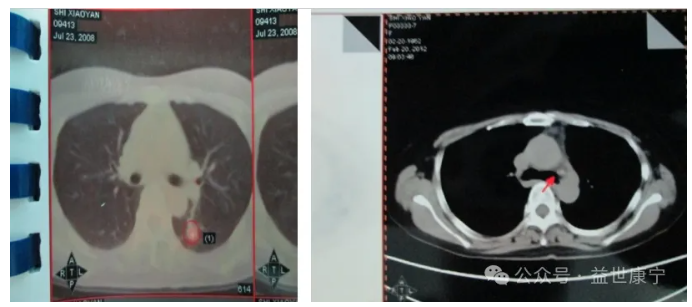

ACTL治疗后影像学图: